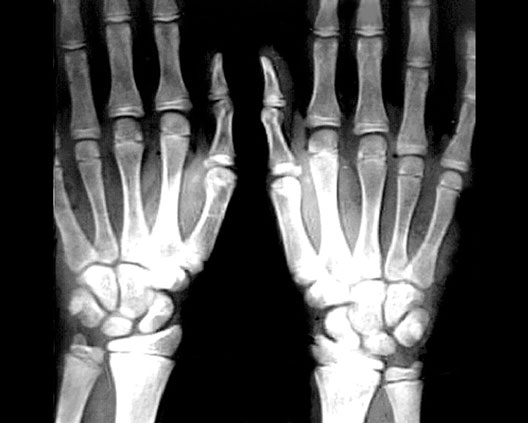

Radiology Images

Wrist Growth Plates

1. Ulnar Growth Plate

2. Radial Growth Plate

3. 2nd Metacarpal Growth Plate

4. 5th Metacarpal Growth Plate

5. 2nd Phalangeal Growth Plate